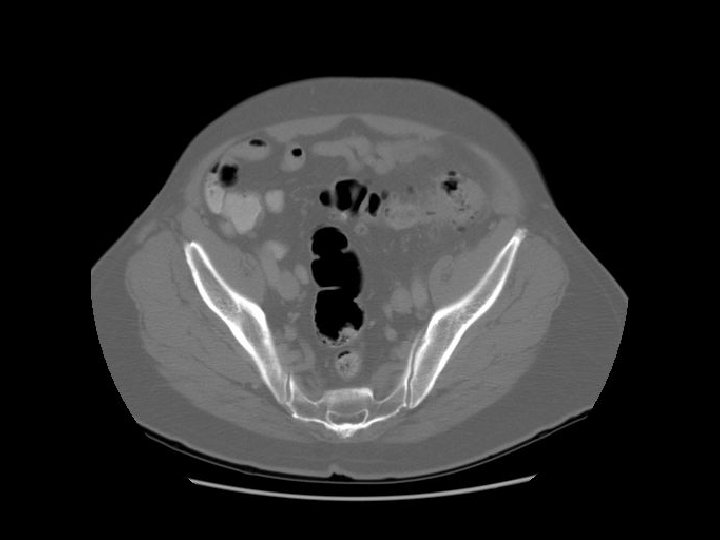

Arrows are pointing to the common iliac veins joining to form the IVC. Left

Ilium Sacrum

Arrows are pointing to the internal and external iliac veins joining to form the common iliac vein.

Rectosigmoid Sacroiliac joint